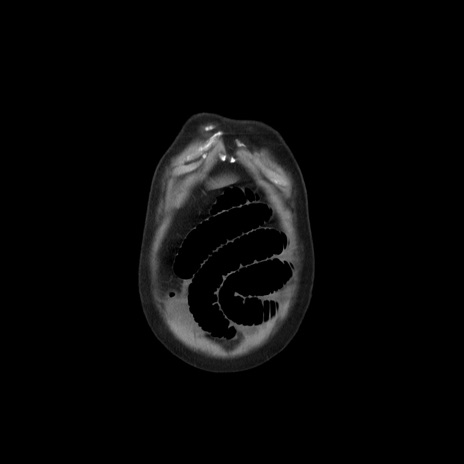

症例20(冠状断像)

【症例】 60歳代男性

【主訴】 腹部膨満、嘔吐

【現病歴】5日前頃より倦怠感を認め食事量減少し4日前の朝嘔吐、食事摂取困難となった。 3日前近医受診し点滴施行され整腸剤などを処方された。 当日他院を受診し、腹部膨満著明、炎症反応の上昇(CRP10.8、WBC11200)あり、紹介受診となる。

【身体所見】 意識JCS1 受け答えがはっきりしないBP 111/57mHg、 P 67bpm、、BT35.2°C、SpO2 97%(RA)、 腹部:膨隆、打診で鼓音あり、全体的に圧痛有り、腸蠕動音(-)、反跳痛ははっきりせず。

【データ】WBC 11400、CRP 14.20

横断像